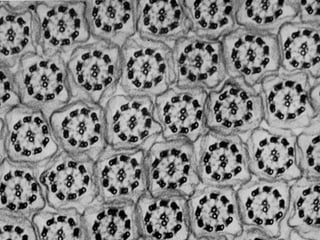

Este documento presenta imágenes microscópicas de diferentes tipos de tejidos y estructuras celulares teñidas con varios métodos histológicos. Incluye fotografías que muestran fibras de colágeno, elásticas y reticulares en diversos órganos, así como membranas basales y células especializadas de órganos como riñones, glándulas mamarias y próstata. El propósito es demostrar la aplicación de técnicas histológicas para visualizar componentes celulares y tej